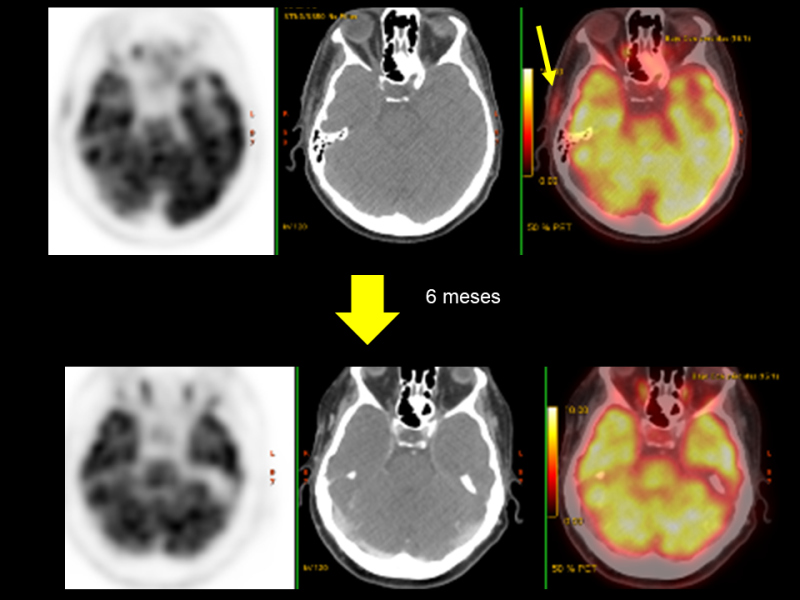

Se realiza PET-CT con 18F-FDG, procedimiento integrado al protocolo de estudio de fiebre de origen desconocido. El resultado muestra aumento de actividad metabólica a lo largo de del cayado aórtico (SUV 7.5), troncos supraaórticos y sus divisiones subclavias-axilares (SUV 6.3-7), carótidas comunes (SUV 5), aorta abdominal (SUV 4.6) y ejes ilíacos (SUV 4.6), interpretándose como arteritis de grandes vasos (Figs. 1 y 2). En la región temporal derecha, coincidiendo con el plano fascial también se identifica aumento de actividad (SUV 3), asimétrico con respecto al lado izquierdo, que se acompaña de alteración de densidad de la grasa, lo que sugiere la presencia de arteritis temporal (Fig. 3).

Se realiza PET-CT de control a los 6 meses de iniciado el tratamiento, que muestra respuesta morfo-metabólica parcial, con disminución de la actividad en grandes vasos incluyendo arteria temporal derecha y mejoría radiológica de las alteraciones inflamatorias circundantes (Figs. 4 y 5). Los datos cuantitativos comparativos (SUV) son los siguientes: